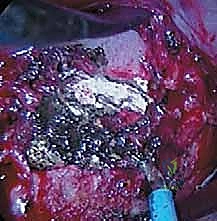

ثامناً: الخطوات الجراحية التفصيلية لعملية الدمج الفقري الأمامي

هذه العملية هي تحفة فنية هندسية وطبية. إليكم كيف يقوم الأستاذ الدكتور محمد هطيف وفريقه الجراحي المتميز بتنفيذها خطوة بخطوة في أفضل مستشفيات صنعاء المجهزة.

هذه خطوة حاسمة لضمان الأمان. يتم توصيل أقطاب كهربائية بجسم المريض لمراقبة وظائف الحبل الشوكي والأعصاب بشكل لحظي (Real-time) طوال فترة الجراحة. أي تغيير في الإشارات العصبية ينبه الجراح فوراً، مما يجعل خطر الشلل شبه معدوم.

الخطوة 3: الشق الجراحي والوص